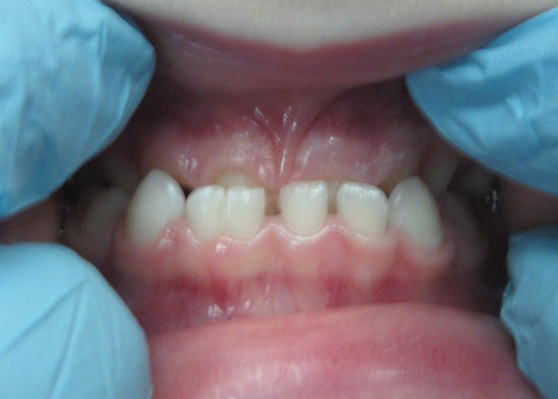

Evie returned to my office for her post-op visit two weeks later. She and her mother were thrilled with the results. Evie hopped right up in the chair and showed me her “new” teeth. It has now been over six weeks since her restorations were placed, and Evie’s mother says, ‘My daughter is so proud of her teeth and shows them off every chance she gets! We are all so amazed with Evelyn’s results, especially Evelyn! She is constantly showing everyone how great her teeth look and how proud she is.’